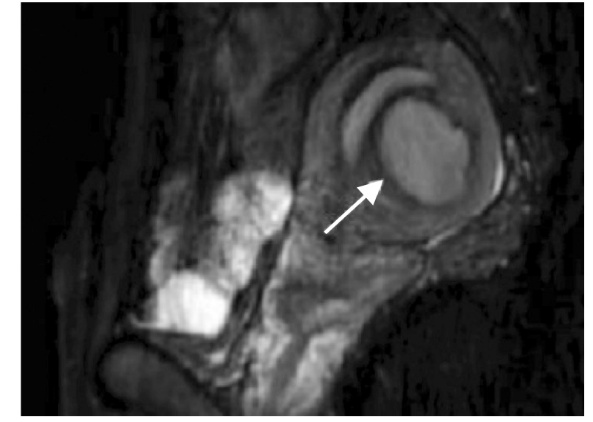

Cystic adenomyosis is a rare type of adenomyosis. Its clinical manifestations are characterized by progressive dysmenorrhea and menstrual abnormalities, accompanied by chronic pelvic pain, dyspareunia and decreased fertility. A case of cystic adenomyosis was reported. The patient was admitted for intermittent lower abdominal pain for more than 3 months. The pelvic MRI combined with carbohydrate antigen 125 (CA125) test suggested the diagnosis of uterine myometrium endometriosis cyst and underwent hysteroscopic resection of endometriosis lesions. Chocolate-like effusion was seen during the operation. With these findings and postoperative pathological results, the patient was diagnosed with cystic adenomyosis. The patient received four cycles of gonadotropin-releasing hormone agonist postoperatively. After 5 months of follow-up, the clinical symptoms were completely relieved and there was no recurrence. The clinical manifestations of cystic adenomyosis have significant heterogeneity. Ultrasound, MRI and CA125 are important auxiliary methods for the diagnosis of this disease. Surgical resection of the lesion is the main means of treatment. Postoperative adjuvant hormone therapy can consolidate the surgical effect, reduce the risk of recurrence and improve the prognosis of fertility.